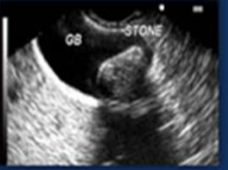

Echogenicity of this

isoechoic

Kidney = hypoechoic to liver

Liver = hyperechoic to kidney

Gallbladder = anechoic

stone = hyperechoic

tumor = hypoechoic to surrounding tissue